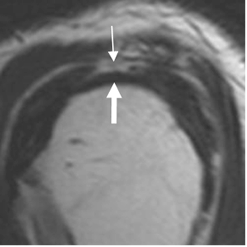

Fig 118. Ruptura parcial del supraespinoso.

RM sagital en T2. Ruptura parcial del tendón supraespinoso en la superficie bursal (Flechas delgadas), con fibras íntegras en la superficie humeral. (Flechas gruesas).